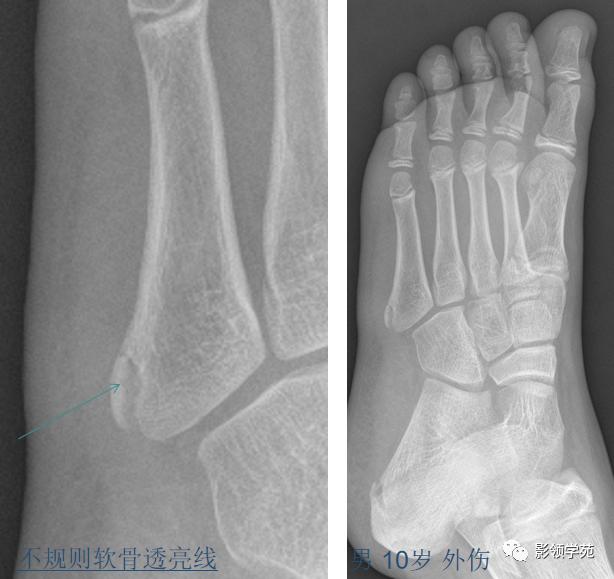

第五跖骨基底部骨折,常为横行骨折,即骨折线垂直于跖骨骨干,它是由于腓侧短肌肌腱应力所引起的撕脱骨折,也称“JONES骨折”。该骨折应与第五跖骨粗隆突起鉴别,尤其是9-15岁的儿童,常常可以出现第五跖骨基底部的骨骺,常表现为纵行透亮线,骨片边缘一般规则光滑,周围软组织无明显肿胀。

第五跖骨粗隆存在独立的骨化中心,并且可有一个或多个骨化中心,常见于10~15岁儿童。一般25岁左右与第五跖骨其余部分融合。

我们所常见的第五跖骨基底部骨折的骨折线一般都是垂直于长轴的,平行于第五跖骨长轴的骨折非常罕见。从外力方向、方式来发现,很难使第五跖骨基底部发生纵形骨折,而该处确实存在骨骺,大量的误诊就是把骨骺当骨折。